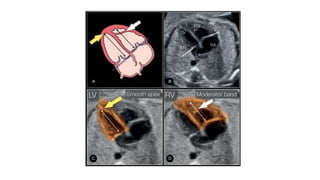

• #17 Schematic drawing and apical four-chamber view (B) with a highlight of the left ventricle (LV) (C) and right ventricle (RV) (D) in a normal fetus, showing the differentiating features of the LV and RV. The LV is longer than the RV (double-sided arrows), is smooth, and forms the apex of the heart (yellow arrow). The RV is coarse and has the typical moderator band (white arrow) in its apex. The tricuspid valve (TV) is shown to insert more apically on the septum than the mitral valve (MV).